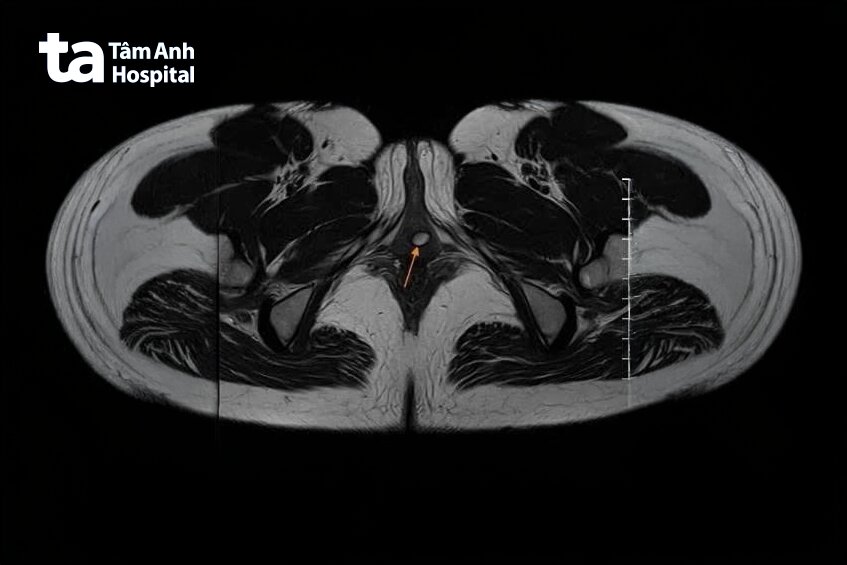

Tại Bệnh viện Đa khoa Tâm Anh TP.HCM, TS.BS Lê Phúc Liên, Trưởng đơn vị Niệu nữ, Trung tâm Tiết niệu – Thận học – Nam khoa khám cho chị Mai, nghi ngờ nguồn gốc của nhiễm trùng là do sự bất toàn vẹn của niệu đạo nên chỉ định chụp MRI. Kết quả chẩn đoán hình ảnh cho thấy người bệnh có túi thừa ở thành sau niệu đạo, kích thước khoảng 5×9 mm.

Ở nam giới, tiểu mủ xuất hiện do các bệnh lây qua đường tình dục, còn ở nữ giới thường do sự bất toàn vẹn của niệu đạo (còn gọi là túi thừa ở niệu đạo). Túi thừa nằm ở đoạn trước phía gần lỗ niệu đạo ngoài, có thể thông với lòng niệu đạo qua một lỗ nhỏ, nước tiểu không thoát ra ngoài mà sẽ đọng lại, gây nhiễm trùng.

Hiện nay, nguyên nhân của túi thừa vẫn chưa được xác định rõ, có thể hình thành do bẩm sinh hoặc mắc phải. Một số dấu hiệu nhận biết bệnh như đau khi đi tiểu, tiểu mủ, nhiễm trùng đường tiểu, nhiễm trùng bàng quang, đau khi quan hệ tình dục, xuất hiện một khối ở thành âm đạo… Tuy nhiên, có trường hợp không xuất hiện triệu chứng cần được chẩn đoán qua thăm khám lâm sàng, nội soi niệu đạo, bàng quang, siêu âm, chụp MRI.